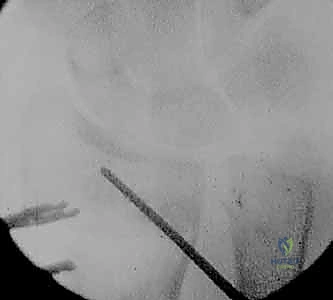

- الأشعة المقطعية (CT Scan) مع إعادة البناء ثلاثي الأبعاد (3D Reconstruction): هذه الخطوة حاسمة. تتيح للدكتور هطيف رؤية العظم من جميع الزوايا، وتحديد مكان القص بدقة متناهية.

3. قص العظم التصحيحي (The Osteotomy)

بناءً على التخطيط الثلاثي الأبعاد المسبق، يستخدم الدكتور هطيف مناشير عظمية دقيقة جداً لعمل شق في العظم في نقطة التشوه الأصلية. يتم فتح العظم وتعديل زاويته واستعادة طوله الطبيعي.